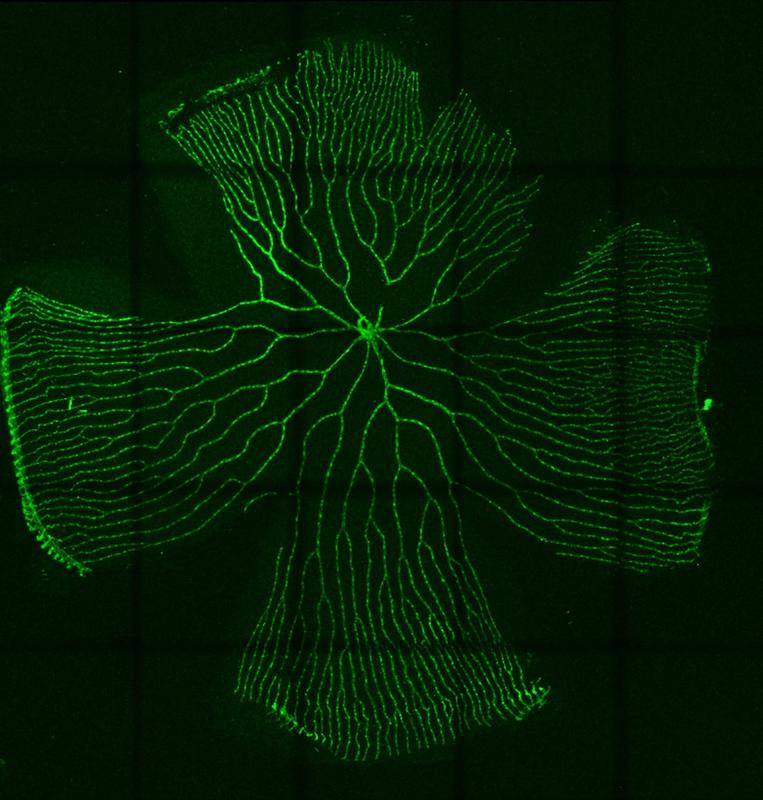

Für seine Forschung nutzt Kroll genetisch veränderte Zebrafische (Danio rerio) mit spezifischen Änderungen im Glukose- und Insulinstoffwechsel, die auch beim Menschen einen Diabetes verursachen. Diese Zebrafische zeigen die typischen Veränderungen in den Blutgefäßen, Augen und Nieren, wie sie häufig in diabetischen Patienten beobachtet werden. Die als diabetische Retinopathie und diabetische Nephropathie bezeichneten Krankheitsbilder gehören zu den mikrovaskulären Folgeschäden der Diabeteserkrankung. Sie können bis hin zur Erblindung und Dialysepflicht führen.

Um diese im Stoffwechsel gebildeten Aldehyde schnell abbauen zu können, hat der Körper vielfältige Schutzmechanismen entwickelt. Was aber passiert, wenn diese Schutzmechanismen ausfallen? Genau diese Frage hat Kroll mit seinem Team untersucht. Die Wissenschaftler deaktivierten im Zebrafisch ein Enzym (Akr1a1a), das im Normalfall das Aldehyd Acrolein unschädlich macht. Die Fische zeigten daraufhin erhöhte Mengen an Acrolein und entwickelten einen Diabetes sowie diabetische Organschäden in Augen und Nieren. Als Ursache zeigte sich eine Insulinresistenz, wie sie genauso auch im Typ 2 Diabetes in diabetischen Patienten auftritt. Die Arbeiten sind aktuell in der hochrangigen Zeitschrift Advanced Science publiziert.